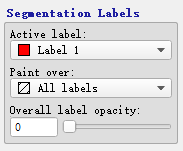

- Segmentation Labels:选择标签

Active label:选择可使用的 Label

Paint over:

Overall label opacity:

在 Active Label 下选择一个标签,然后基于此标签进行分割

Paint over 为 all labels,表示分配的标签将覆盖掉已经有标签的 voxels

注:记得将 Overall label opacity 调大一点,不然看不到标签